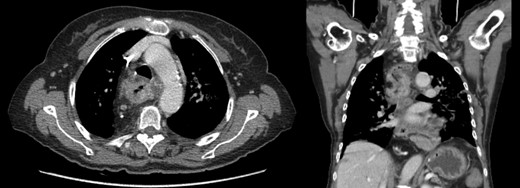

Staging with chest, abdomen and pelvic tomography, showed no signs of regional spread or metastatic disease (Fig. 2), and positron emission tomography scan revealed FDG (fluorodeoxyglucose) avidity in the primary lesion (retrosternal colic tube with thickened walls) and regional lymph nodes (Fig. 3).